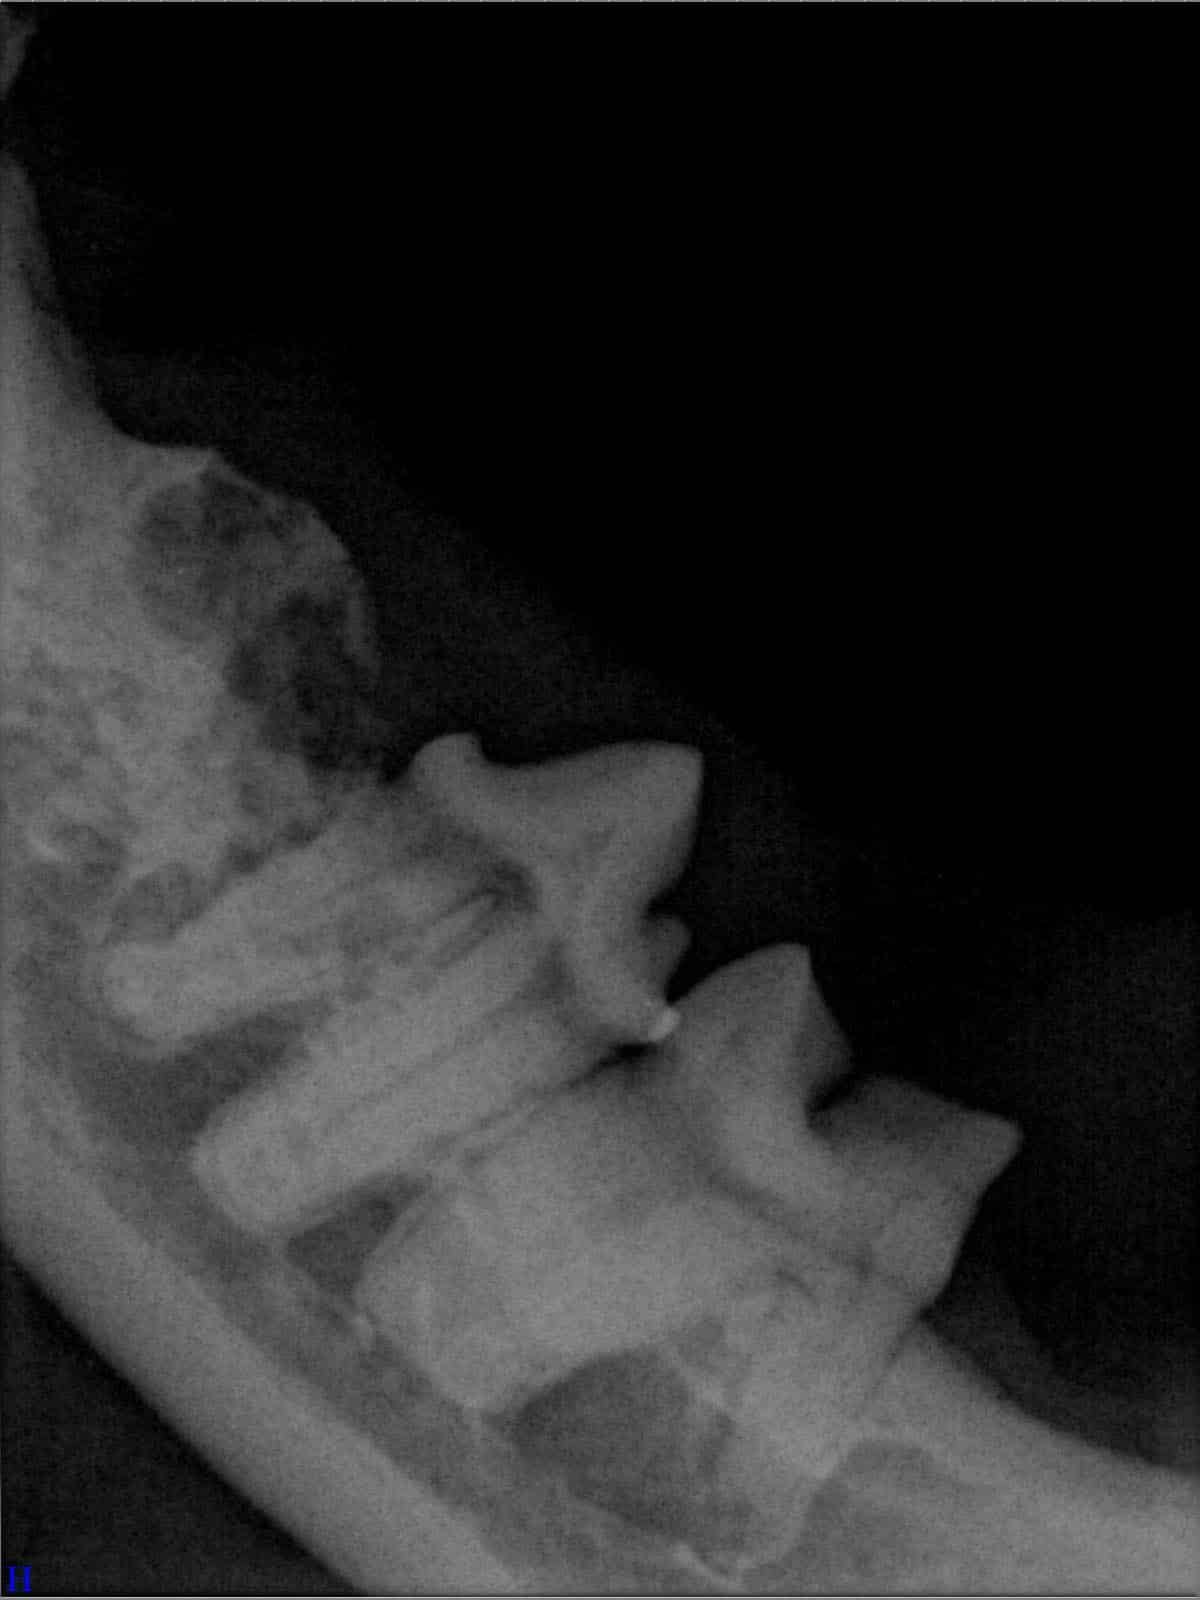

Röntgenbilder

(Fraktur + Wurzelentzündung durch Zahnstein)

Um das Ausmaß von Zahnstein und möglichen Folgeschäden richtig zu beurteilen, ist eine tierzahnärztliche Untersuchung erforderlich. Neben der Sichtkontrolle werden häufig Röntgenaufnahmen der Zähne angefertigt, um Entzündungen oder Veränderungen unter dem Zahnfleisch zu erkennen. So kann der Tierarzt gezielt entscheiden, welche Zähne erhalten werden können und wo eine Behandlung notwendig ist. Eine frühzeitige Diagnostik hilft, Schmerzen zu vermeiden und die Zahngesundheit des Hundes langfristig zu sichern.